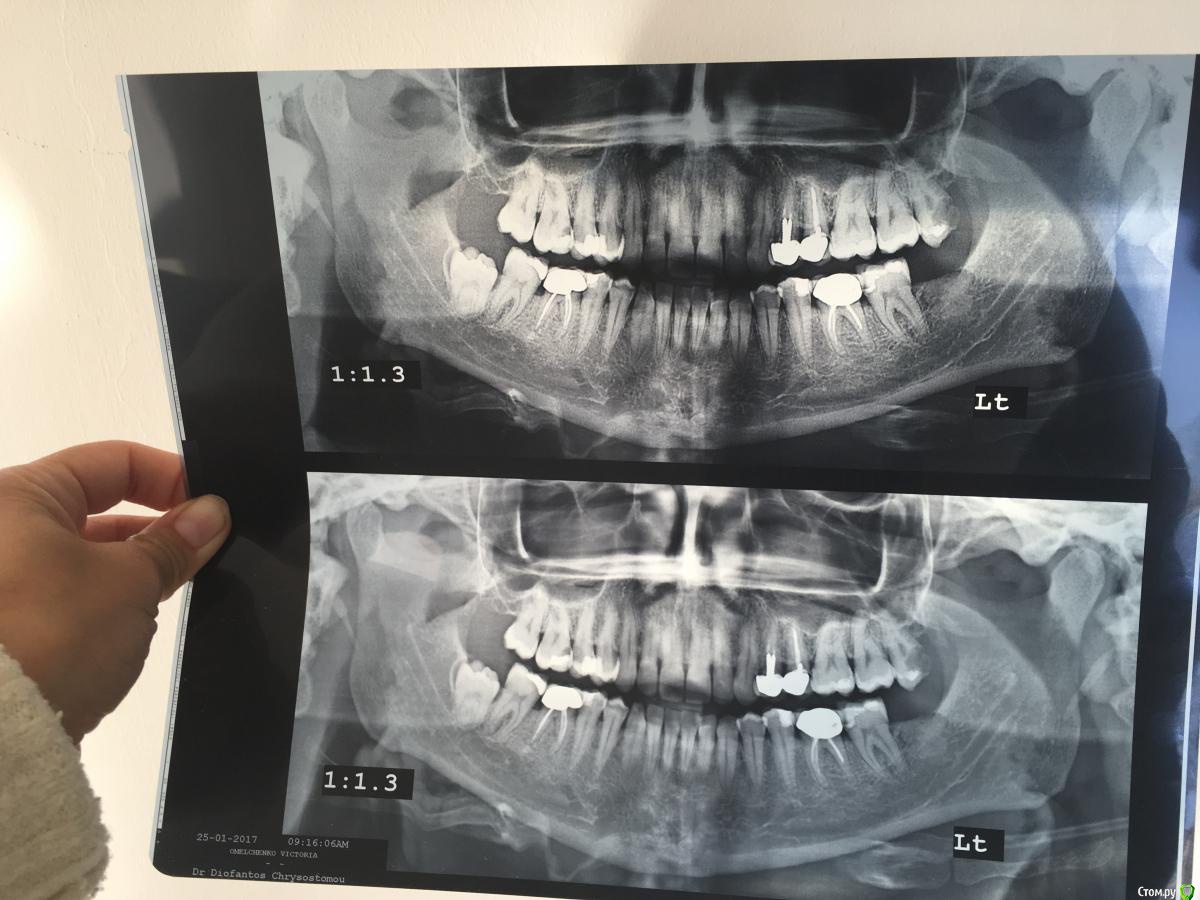

ВикаКипр Опубликовано 26 января, 2017 Поделиться Опубликовано 26 января, 2017 Вот мой снимок <A href="http://www.fayloobmennik.net/6829563">image.jpeg</A> Уже 4 сутки нескончаемая боль в левой части челюсти. По общениям-низ.Доктор посмотрел рот, сделали снимок.Выписал антибиотик, amoxicillin 875 и обезболивающее Diclofenac 75. Начались третьи сутки на таблетках.Боль не уходит, поменяла диклофенак на Найз.Но и его не достаточно.Ночью сплю со снотворным, невозможно спать. Терпеть боль могу, скорее всего это помогают таблетки. Боль на 7 баллов из 10. В моментобращенич к доктору были все 10 из 10. Вопрос: Доктор сказал пить антибиотик 7 дней, на 6 день назначил удаление 8 сверху слева. У меня болит больше Низ, нежели верх. Посмотрите на снимок, может мы что-то пропустили!? Мне вообще будет легче!? И когда!? Ссылка на комментарий

red_butler Опубликовано 26 января, 2017 Поделиться Опубликовано 26 января, 2017 Нужно смотреть зубы 3.5 и 3.7 на предмет пульпита. А восьмерку удалить в ближайшее время. Ссылка на комментарий

DmitrySH Опубликовано 26 января, 2017 Поделиться Опубликовано 26 января, 2017 Верхнюю восьмерку удалите побыстрее. По снимку она может давать все боли. Ссылка на комментарий